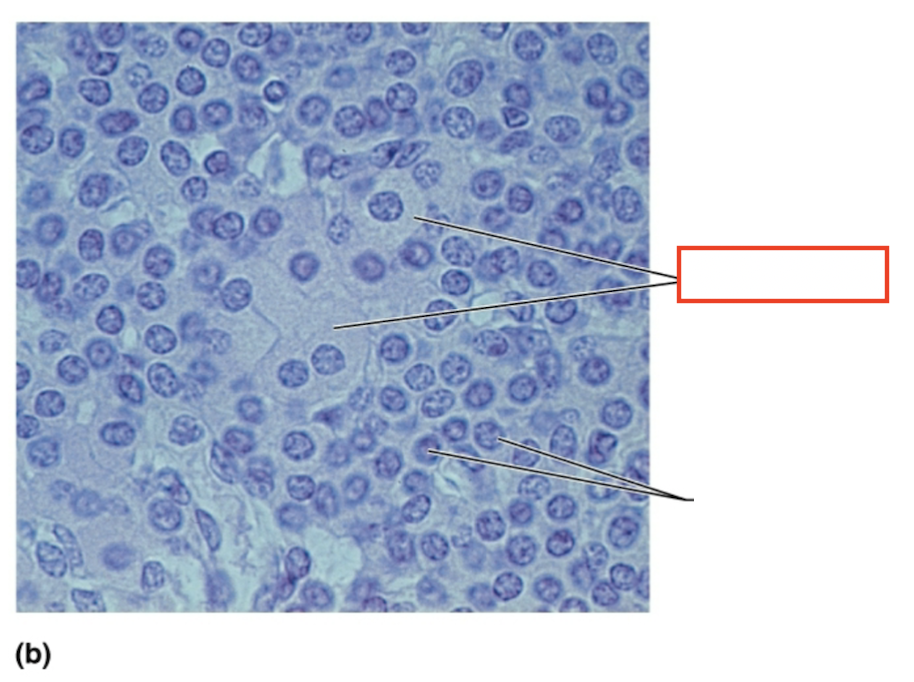

What structure is highlighted?

acidophils

What structure is highlighted?

chromophobe

What structure is highlighted?

basophil

What tissue is shown?

anterior pituitary